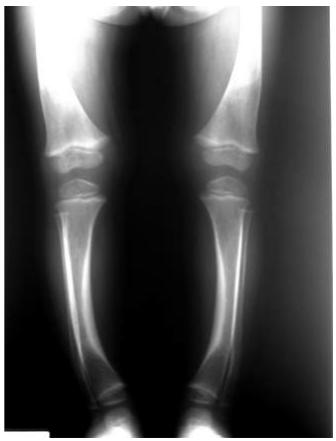

Blount’s Disease

Indications: X-ray when severe or possibly pathologic

Recommended Views:

- Standing AP film: Long film (hips to ankles) with patellae directed forwards

Radiological Parameters to Assess:

- Medial Physeal Slope

- Femoral-Tibial Axis

Tibia vara (Blount’s disease)